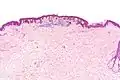

Intermediate magnification

Micrograph of a dysplastic nevus showing the characteristic rete ridge bridging, shouldering, and lamellar fibrosis. H&E stain.